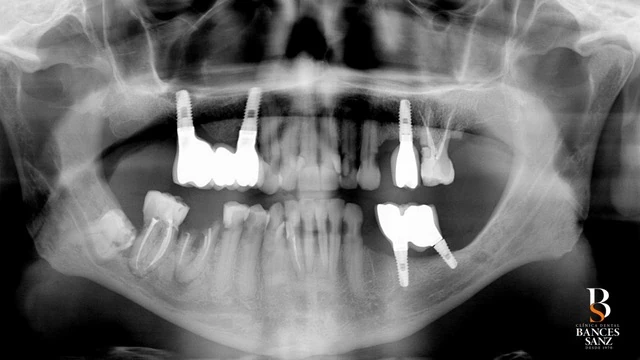

- En la arcada superior existían tres implantes, de los cuales dos pudieron conservarse, mientras que uno no presentaba condiciones adecuadas para su mantenimiento.

- En la arcada inferior, los implantes existentes no pudieron ser conservados, siendo necesaria su retirada.

Se planificó una rehabilitación oral completa bimaxilar mediante la técnica All-on-6, colocando seis implantes en cada arcada, e integrando los implantes que sí podían mantenerse dentro del plan global.